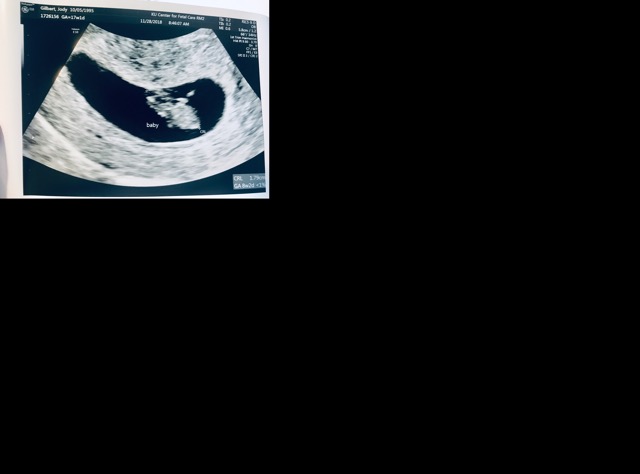

8 weeks 2 days

Had my second ultrasound done today and saw my rainbow baby move and the heartbeat for the first time. The baby had a heart rate of 167 so I’m hoping that means it’s a girl 💝